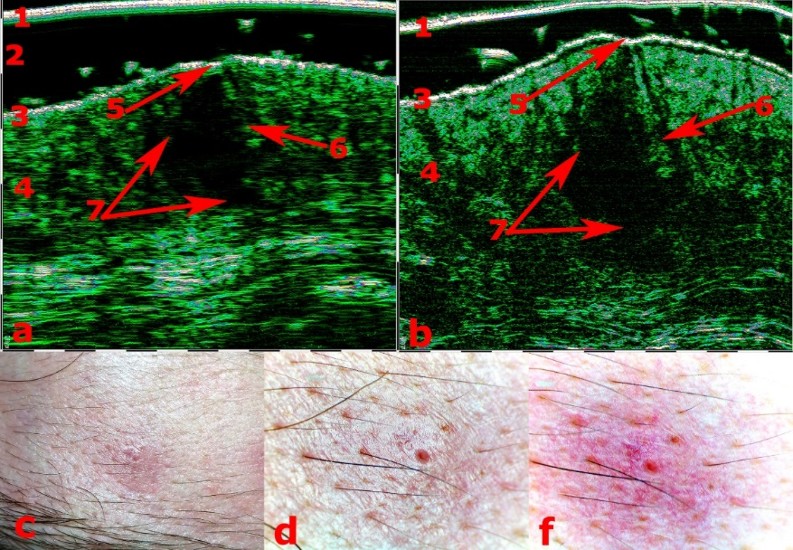

Εικόνα 1- Ψωριασική βλατίδα πριν από τη βιοψία με υπέρηχο 75 MHz (αριστερά)

Εικόνα 2- Η ίδια ψωριασική βλατίδα σε ιστολογική εικόνα

Εικόνες 3,4 – Εικόνες βιντεοδερμοσκόπησης κατά αντιστοιχία

Εικόνα 1- Εικόνα Βασικοκυτταρικού Καρκινώματος με υπέρηχο 30MHz

Εικόνα 2- Εικόνα Βασικοκυτταρικού Καρκινώματος με υπέρηχο 75MHz

Εικόνα 3- Εικόνα CFM (Control Focal Microscopy: Μικροσκόπηση Ελέγχου Εστίασης) με υπέρηχο 18MHz

Εικόνες 4,5- Εικόνες Βιντεοδερματοσκόπησης

Εικόνες 6,7- Ιστολογικές εικόνες μετά από χειρουργική αφαίρεση

1 – Εικόνα BCC με υπέρηχο 30MHz

2 – Εικόνα BCC με υπέρηχο 75MHz

3,4 – Εικόνες Βιντεοδερματοσκόπησης